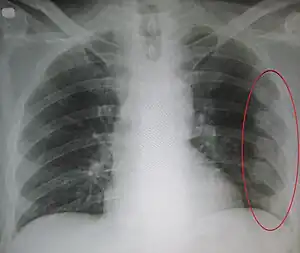

![]() | |

| An X ray showing multiple old fractured ribs of the person's left side as marked by the oval. | |